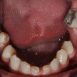

Interdisciplinary Treatment of Patients with Deep Overbite and Parafunctional Activity

Bruxism is defined as parafunctional grinding of teeth and due to the excessive wear of the posterior teeth, patients with long-standing bruxism often have pathological deep overbite. For many decades, treatment of bruxism and deep overbite was focused on reshaping the bite for achieving an occlusion free of deviations. Despite large efforts, the management of bruxism and subsequent deepening overbite was not obtained.